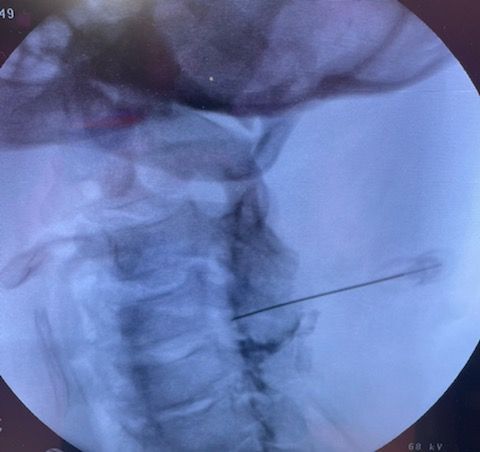

Starszy Asystent w Klinicznym Oddziale Neurochirurgicznym oraz Poradni Neurochirurgii Wojewódzkiego Szpitala Specjalistycznego im. św. Barbary nr 5 w Sosnowcu. Konsultant Kliniki Neurologii Szpitala Klinicznego nr 1 w Zabrzu. Absolwent Wydziału Lekarskiego Śląskiego Uniwersytetu Medycznego w Zabrzu. Staż podyplomowy odbył w latach 2010-2011 w Oddziale Neurochirurgii WSS nr 4 w Bytomiu. W 2018r. złożył egzamin specjalizacyjny po zakończeniu szkolenia w ramach rezydentury w WCM Opole. W 2019 roku uzyskał stopień doktora nauk medycznych. Specjalizuje się w kompleksowym leczeniu schorzeń kręgosłupa (dyskopatia, stenoza kanału kręgowego, kręgozmyk) oraz neuroonkologii. Szczególny zakres działań medycznych to nowoczesne, małoinwazyjne operacje kręgosłupa z wykorzystaniem technik endoskopowych (mikrodiscektomia - implanty rozprężalne), przezskórnych stabilizacji oraz mikrochirurgicznych dekompresji. Wykonuje procedury iniekcyjne; discoGEL, GelSTIX, kriolezje oraz blokady przeciwbólowe kręgosłupa odcinka szyjnego, lędźwiowo-krzyżowego a także stawów krzyżowo-biodrowych, które odgrywają istotną rolę w procesie diagnostyczno-leczniczym wielu zespołów bólowych. Na co dzień przeprowadza operacje w ramach kontraktu z NFZ. Członek Polskiego Towarzystwa Neurochirurgów oraz Polskiego Towarzystwa Chirurgii Kręgosłupa. Uczestnik wielu krajowych i zagranicznych kursów neurochirurgicznych, m.in. w Czechach, Słowacji, Niemczech, Włoszech, Danii, Austrii, Szwajcarii i USA. Autor licznych publikacji naukowych.

Zdjęcia i filmy